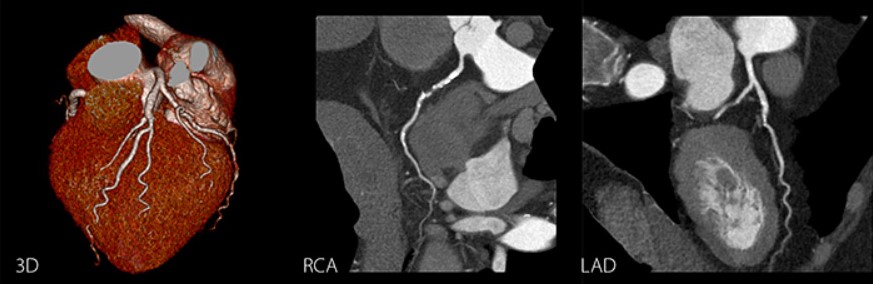

Robust cardiac CT examinations - automated, adaptive and easy

Cardiac CT imaging has never been more robust than with the Aquilion Prime SP. The intelligent SURECardio engine is coded with the experience of thousands of cardiac examinations, ensuring scan and exposure parameters adapt exactly to your patients in real time.